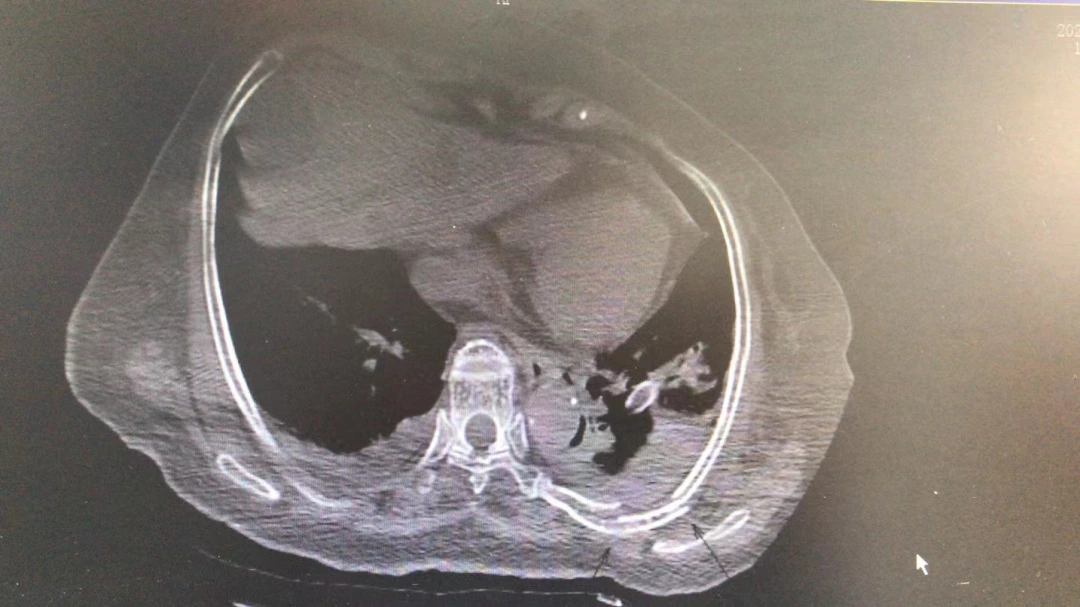

今年2月底的一天,80岁的刘奶奶在家门口被一辆三轮车撞倒,车从她的胸部轧了过去。刘奶奶被紧急送往当地医院重症监护室,检查结果让医生吃惊:CT成像显示断了22根肋骨,也就是除了最粗短的第1肋,两侧的2-12肋全部断裂,且合并肺挫裂伤、血气胸和耻骨骨折。

胸部横断面CT